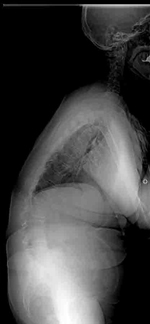

特に最も多い胸椎が右に弯曲する側弯症ではアダムステストと呼ばれる体幹を前に屈めるテストを行うと、右の背中が盛り上がります。痛みや機能の障害を伴うことは比較的稀です。

手術の最大の目的は側弯の進行の予防です。進行の確率は、10~12歳の場合、コブ角30度以上の側弯では約90%の確率で、コブ角60度以上の側弯の場合は100%の確率で進行します。仮に重度の側弯症になった場合、疼痛や整容的な問題にとどまらず、肺機能の低下(息切れ)が生じます。これは脊柱の変形によって肺が圧迫されるためです。骨の成長終了後(18-20歳以上)もコブ角が40度を超えた側弯症は年間0.5~1度程度の進行があるといわれております。成長終了後の側弯症では、今後の側弯の進行の可能性と手術の危険性などを主治医と相談して、手術を受けるかどうか決めたほうが良いと考えられています。